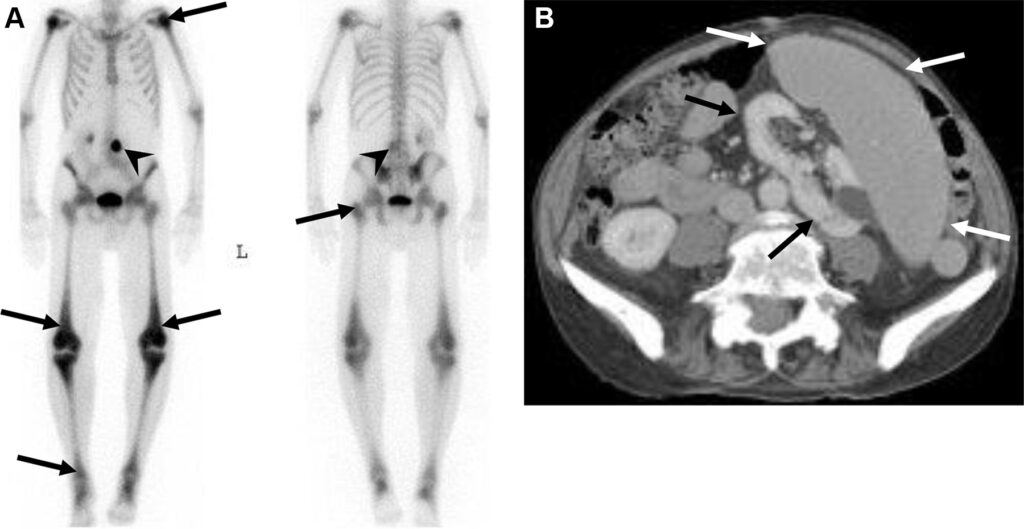

Metastasi costali e pleuriche con versamento pleurico in una donna di 63 anni con tumore al seno.

La scintigrafia ossea con 99mTc-MDP evidenzia una lieve ipercaptazione diffusa che ricalca l’emitorace destro, causata verosimilmente dall’accumulo di tracciante nel liquido pleurico maligno. È inoltre visibile una captazione longitudinale a carico dell’arco posteriore dell’XI costa destra. La TC conferma la natura della captazione, evidenziando il versamento pleurico, un ispessimento pleurico e le iniziali alterazioni osteosclerotiche a carico della costa interessata. Il caso dimostra come la scintigrafia ossea possa rilevare non solo le localizzazioni secondarie scheletriche dirette, ma anche segni indiretti di patologia extra-ossea adiacente (come la captazione pleurica).